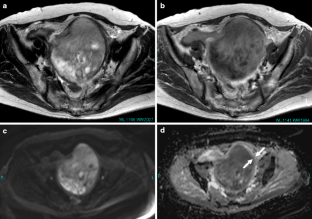

Fig. 7a–d